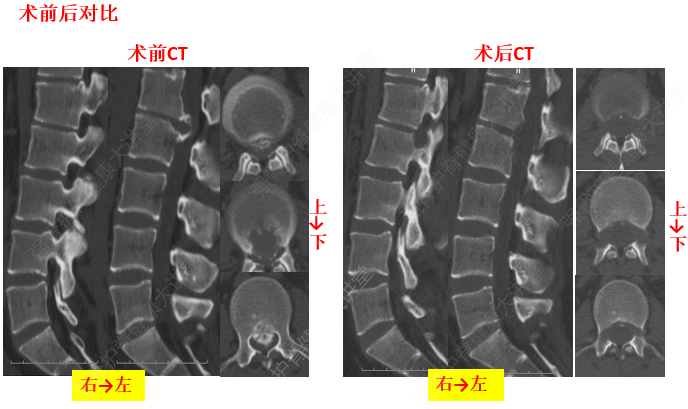

由于頸椎關(guān)節(jié)突間關(guān)節(jié)面近乎水平位,一旦椎間盤(pán)發(fā)生退變、椎間隙即變窄,關(guān)節(jié)囊及韌帶松弛,加上頸部活動(dòng)時(shí)重力的影響,即可造成積累性損傷,加速頸椎退變和不穩(wěn),導(dǎo)致頸椎關(guān)節(jié)發(fā)生移位,使椎間孔變狹,椎管徑發(fā)生改變,壓迫神經(jīng)根或脊髓,產(chǎn)生臨床癥狀與體征。